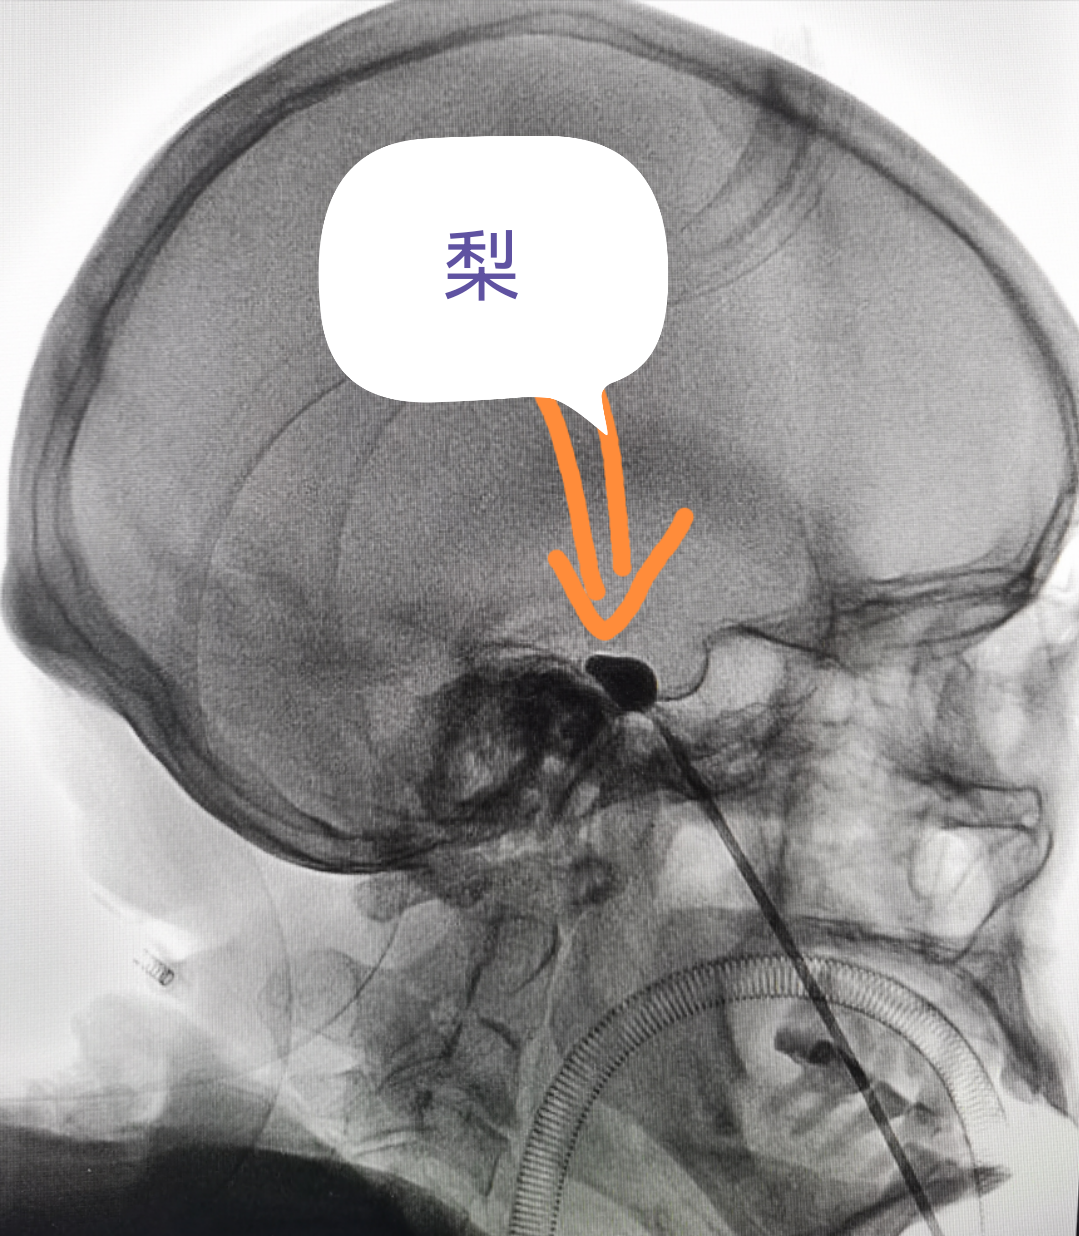

看到這個“梨”,你會想到什么?

專業(yè)醫(yī)生卻會說:ta和我們的

治療三叉神經(jīng)痛中微創(chuàng)技術(shù)在影像上的呈現(xiàn)挺像噠

(看著像梨,哈哈...)

經(jīng)過面部口角處穿刺到三叉神經(jīng)半月節(jié)內(nèi),放入球囊,向球囊里打入對比劑,使球囊擴張,完美顯示一個“梨”形,壓迫3-5分鐘,壓迫毀損感覺神經(jīng),保留運動神經(jīng),阻斷疼痛信號傳導(dǎo),達到止痛目的。適合單支或多支發(fā)病患者,尤其高齡、合并癥多,不愿意接受開顱手術(shù)患者。術(shù)后面部稍有麻木。